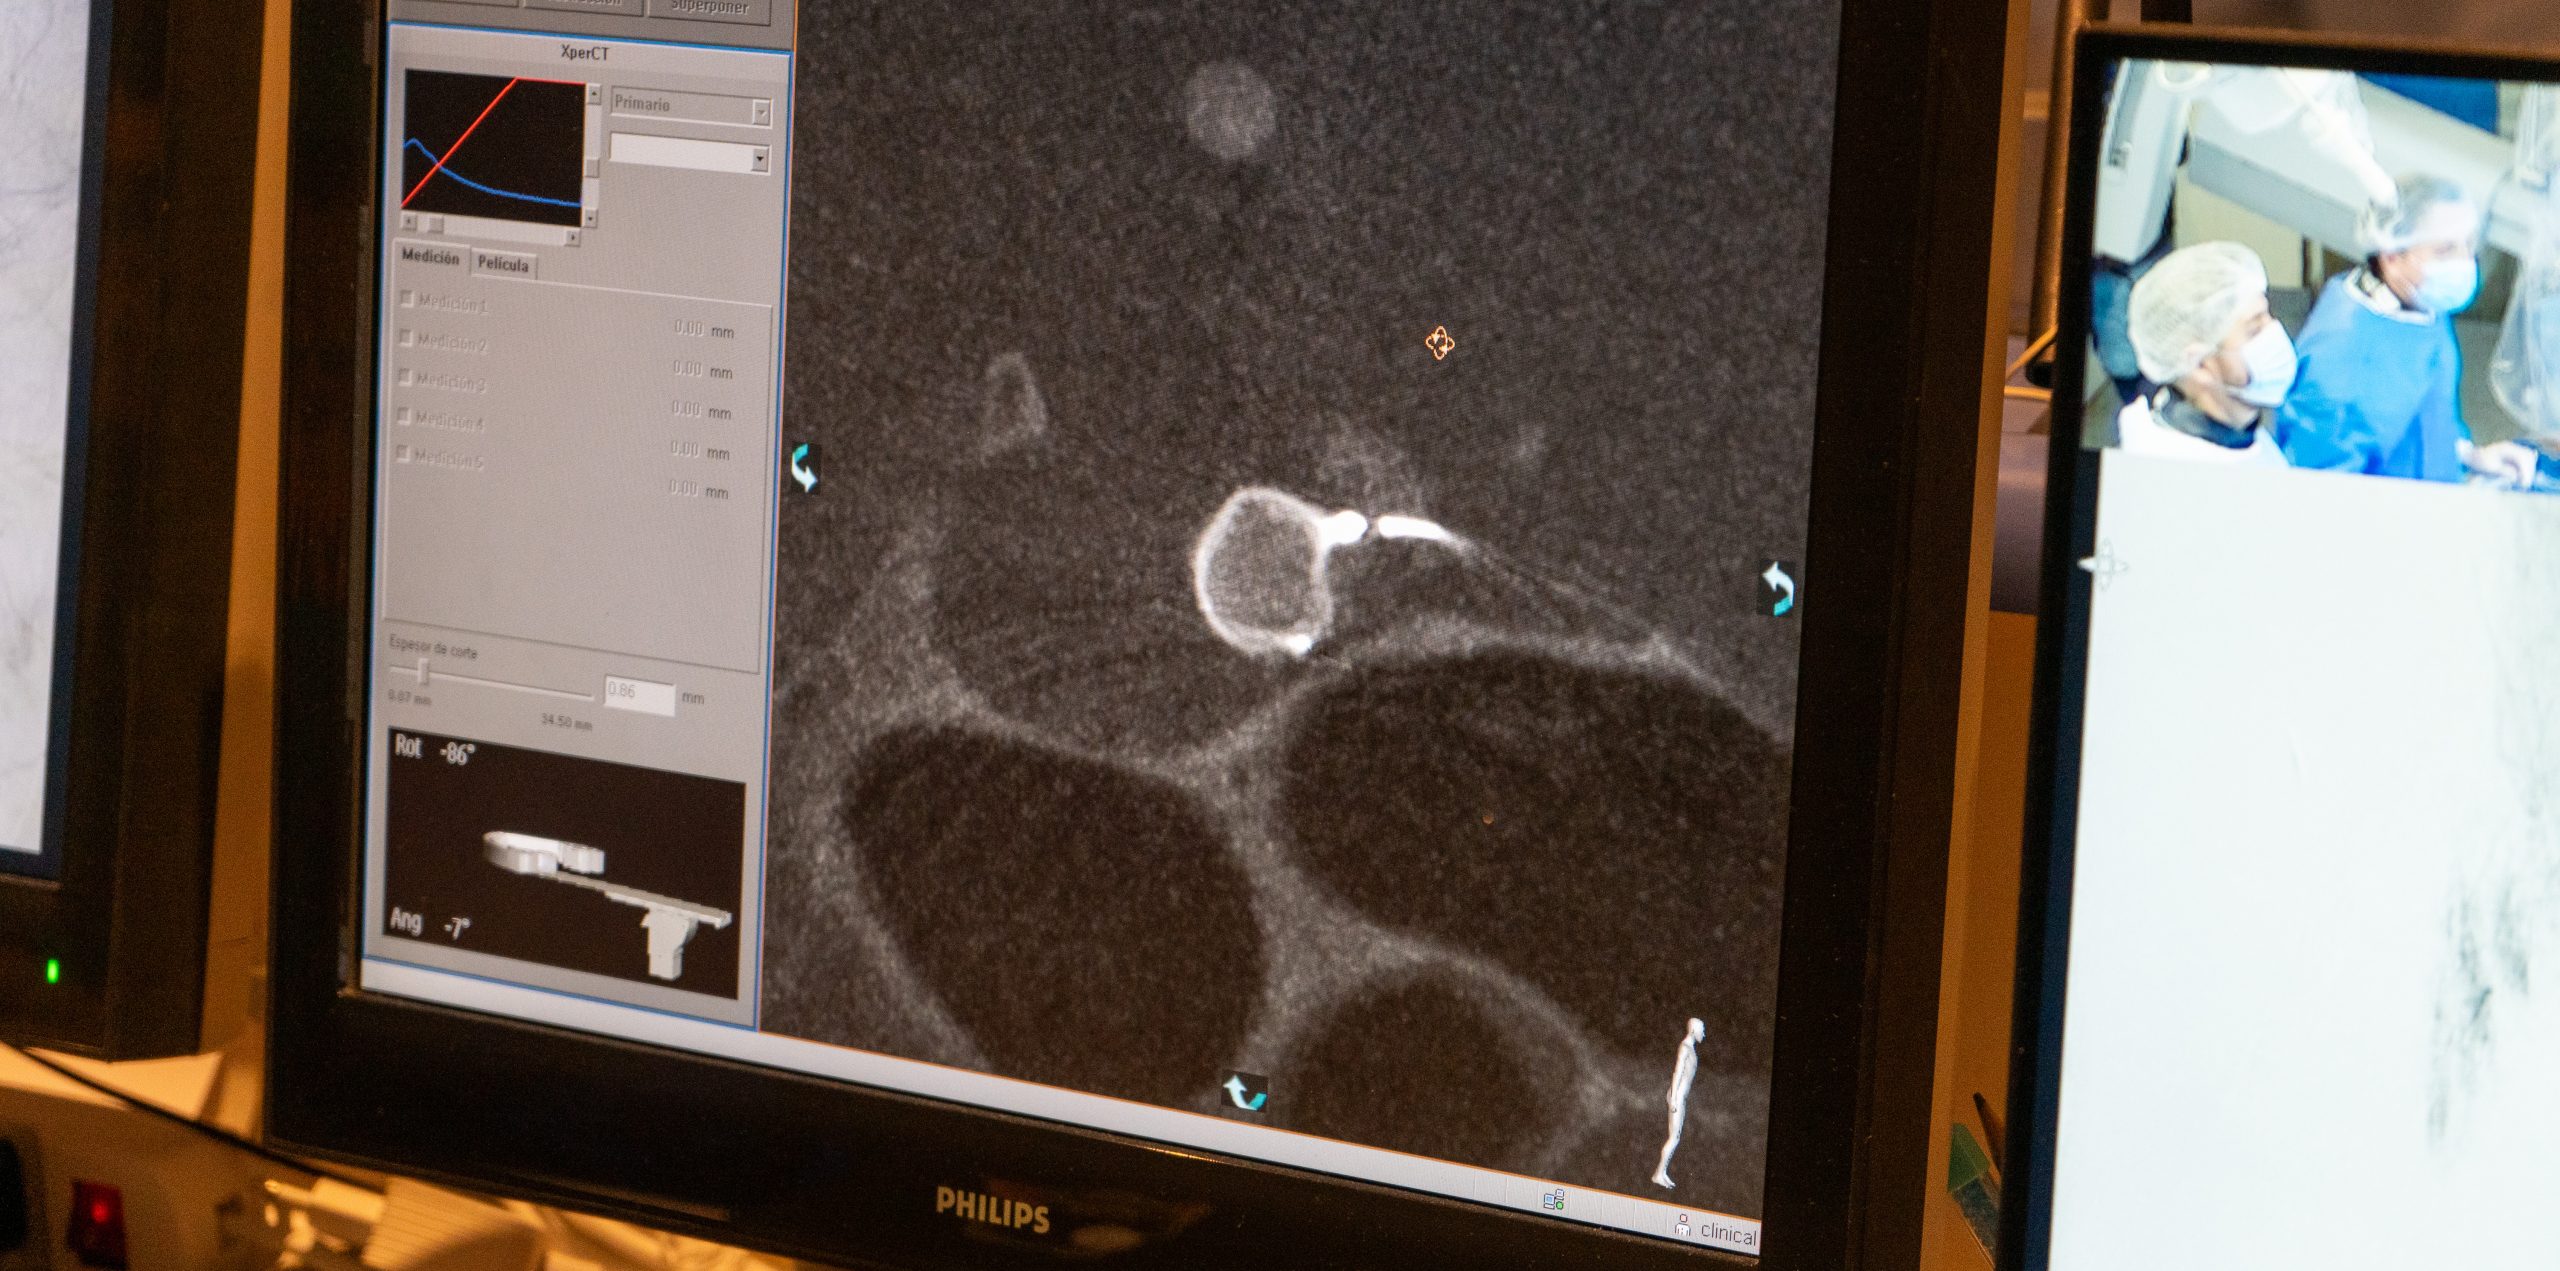

El dispositivo, denominado artemisse, es una diminuta pieza de nitinol (aleación de níquel y titanio) que se expande como un globo y se ajusta a la forma del aneurisma. Al rellenar el vaso, facilita una trombosis progresiva que culmina en la oclusión completa de la arteria dañada y evita el riesgo de un accidente cerebrovascular hemorrágico, de alta mortalidad.